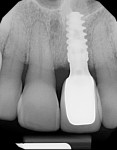

After 3 months, the patient returned for evaluation of implant osseointegration and soft-tissue healing. The ETPC and temporary abutment were removed, and secondary stability of the implant was confirmed with a reverse-torque test up to 20 Ncm.13 The peri-implant soft tissue had stabilized coronally and was now even with the adjacent central incisor (Figure 11). The soft-tissue profile appeared thicker, with an increase in attached keratinized tissue. A periapical radiograph demonstrated bone healing around the implant and bone fill of the socket spaces (Figure 12). An occlusal view of the peri-implant tissue showed the ridge contour had been reestablished and an anatomic emergence profile had developed around the ETPC (Figure 13). The patient returned to her restorative dentist for the final abutment and crown fabrication. A cement-retained porcelain-fused-to-metal implant-supported crown was fabricated, and the incisal edges of the other maxillary teeth were recontoured to improve esthetics (Figure 14). Bone and soft-tissue levels remained stable after 1.5 years and probing depths around the implant were limited to 1 mm to 2 mm with no bleeding on probing (Figure 15). The patient was satisfied with the final result.